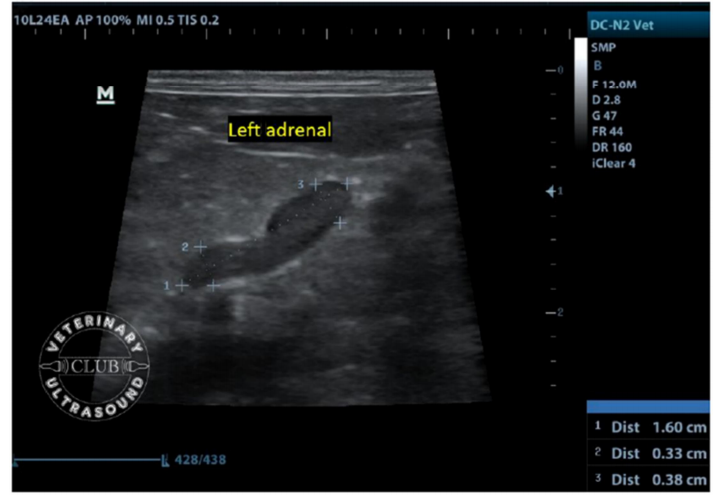

在上述研究中,作者认为12公斤以下犬的肾上腺尾极不应大于0.62厘米,体重≥12公斤犬的肾上腺尾极不应大于0.72厘米。

内科医生总是需要对怀疑肾上腺机能亢进/减退的动物进行评估,肾上腺的超声评估有助于鉴别HAC的动物是PDH还是FAT以及对肾上腺肿瘤进行分期。90%的肾上腺皮质功能亢进犬存在双侧肾上腺的肿大,而罹患肾上腺肿瘤的动物的典型表现为一侧可见肿瘤,对侧腺体萎缩。这具有高度的特异性。肾上腺的超声在对于怀疑库兴的动物上有着重要的意义,而了解正常肾上腺的超声扫查,对怀疑肾上腺问题犬猫的超声检查来说,则是重要的第一步。